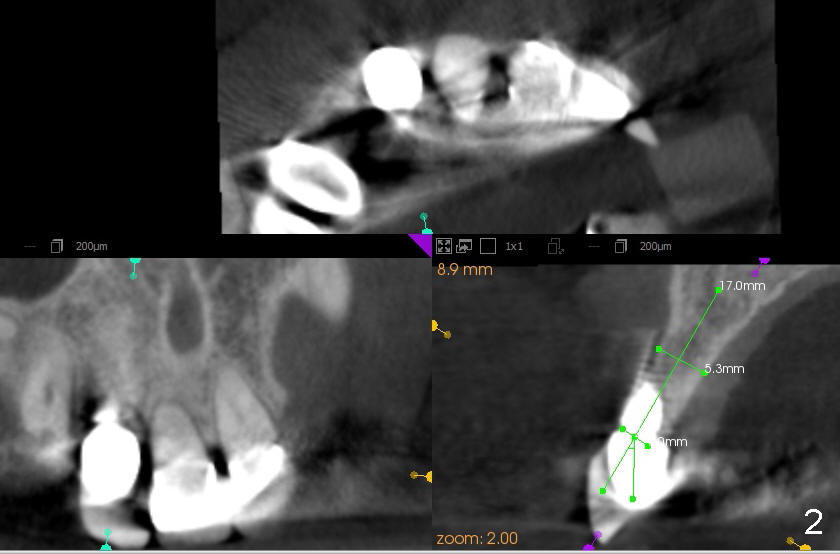

The fourth case: Female 65yrs heathy,#6 fractured below gum line, #7 implant mobility II, did 6 months ago . she is a tiny typical Chinese, with small jaw. I am planning to take 6 (root), and #7 implant out, put on two implants into #6 and #7 sockets, bone graft as well.

CBCT studies reveal that the implant perforates the buccal plate at the site of #7 and that there is still enough bone to support 3.0x17 mm one piece implant (Fig.2,3).  There is limited bone apical to the tooth #6.  The implant should be at least 17 mm for bone level and 14 mm for tissue level (Fig.4) or preferably 20 mm with sinus lift (Fig.5).  The diameter will be 4.5 mm (Fig.6) or 5 mm (Fig.4.5).

For cosmetics, the tooth #6 and the implant #7 should be removed without flap.  Two immediate provisionals are to be fabricated separately and bonded with composite after cementation.